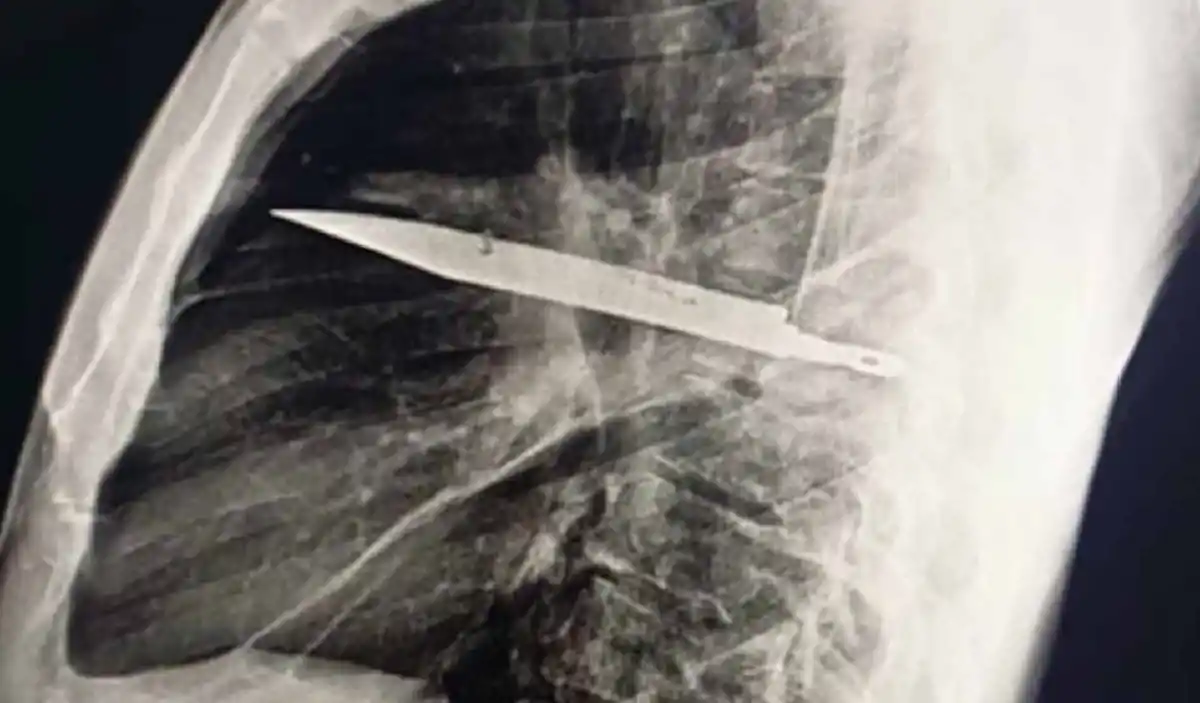

Una radiografía de tórax reveló la impactante verdad: un objeto metálico retenido, identificado como un cuchillo completo, había penetrado a través de su escápula y estaba rodeado de pus y tejido necrótico, generando la infección que finalmente lo llevó a buscar ayuda médica.